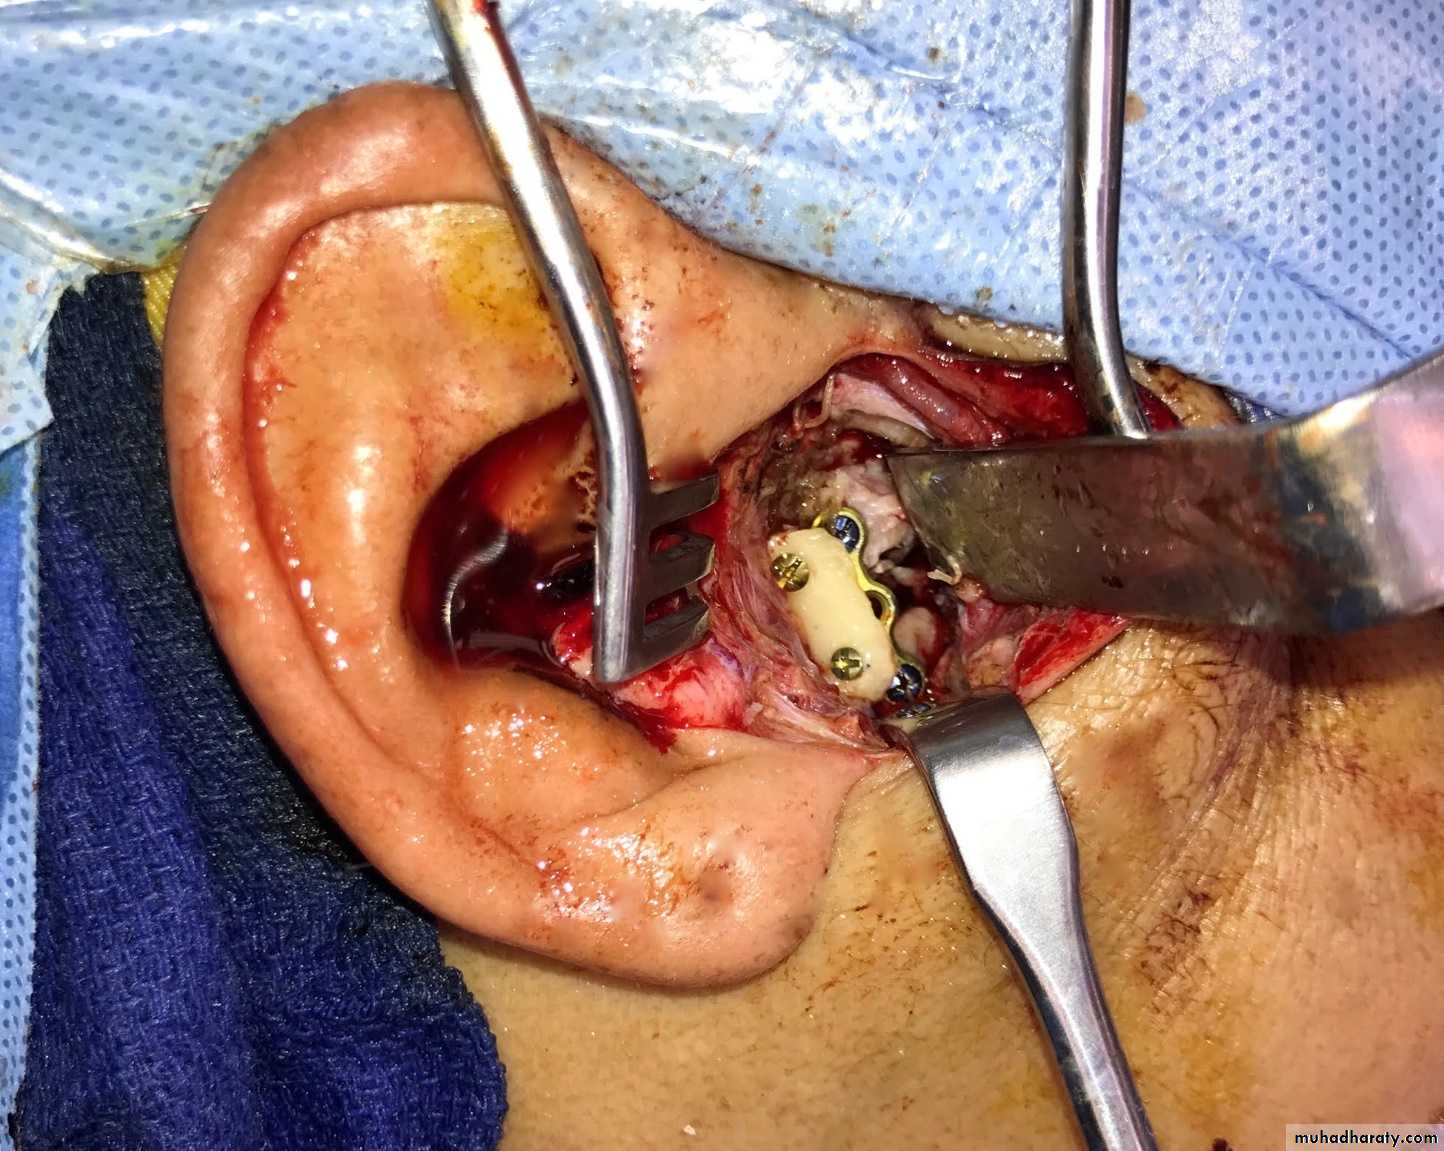

Condylectomy

• Condylar head of a fibrosed joint is removed.

• Approached through a preauricular incision.

• Once the neck of the condyle is cut, the cut condylar head is removed, pressure pack is given

• IMF is done for a few days followed by active mouth opening exercise.

• Care should be taken to avoid injury to the maxillary artery, as it lies just below the neck of the condyle.